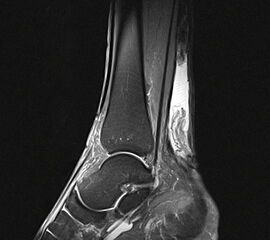

• MRT des Rückfußes:

• Beurteilung der Achillessehne und des Ausmaßes des Schädigung

• Nachweis von fettigen Degenerationen des M. gastrocnemius und des M. soleus.